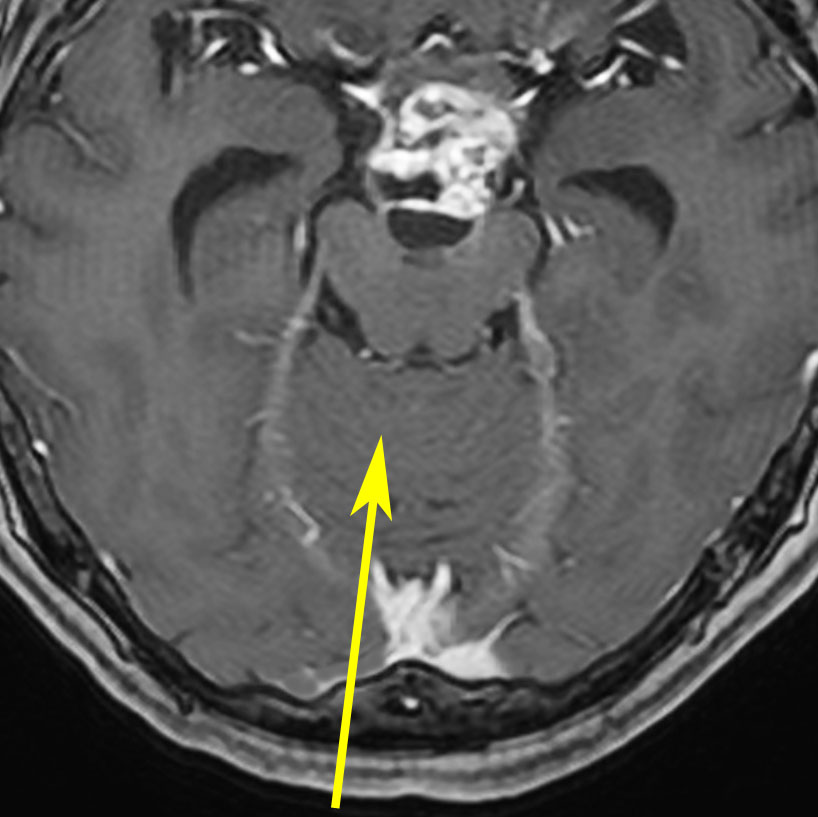

小さな松果体奇形腫です。

OTAでこの奇形腫を見ようとする場合に,テントを静脈洞交会の低い位置まで切断しなければ,直静脈洞の横から松果体部をみることはできません。また,黄色の矢印の方向に視野が入るので,まず最初に邪魔になるのは小脳上極です。上小脳層を左右ともに十分剥離すると,小脳が可動化して,その向こうに,precentral cerebellar veinが見えます。このveinをガレン大静脈への流入部から小脳前面に沿って剥離していくと,小脳上極がさらに可動化して松果体への視野が開ます。

松果体腫瘍の手術では,中脳背面を見る必要があります。特に上丘とそれに連続する後交連 posterior commissureを十分に観察するために周囲組織の剥離を行います。具体的には迂回槽と下丘の周囲のクモ膜組織を剥離します。対側中脳と迂回槽を見る時に妨げになるのが,緑の矢印で示した直静脈洞です。テントが長く切断してあって直静脈洞が大脳鎌と一緒に動かせると対側を見るのがとても簡単になります。